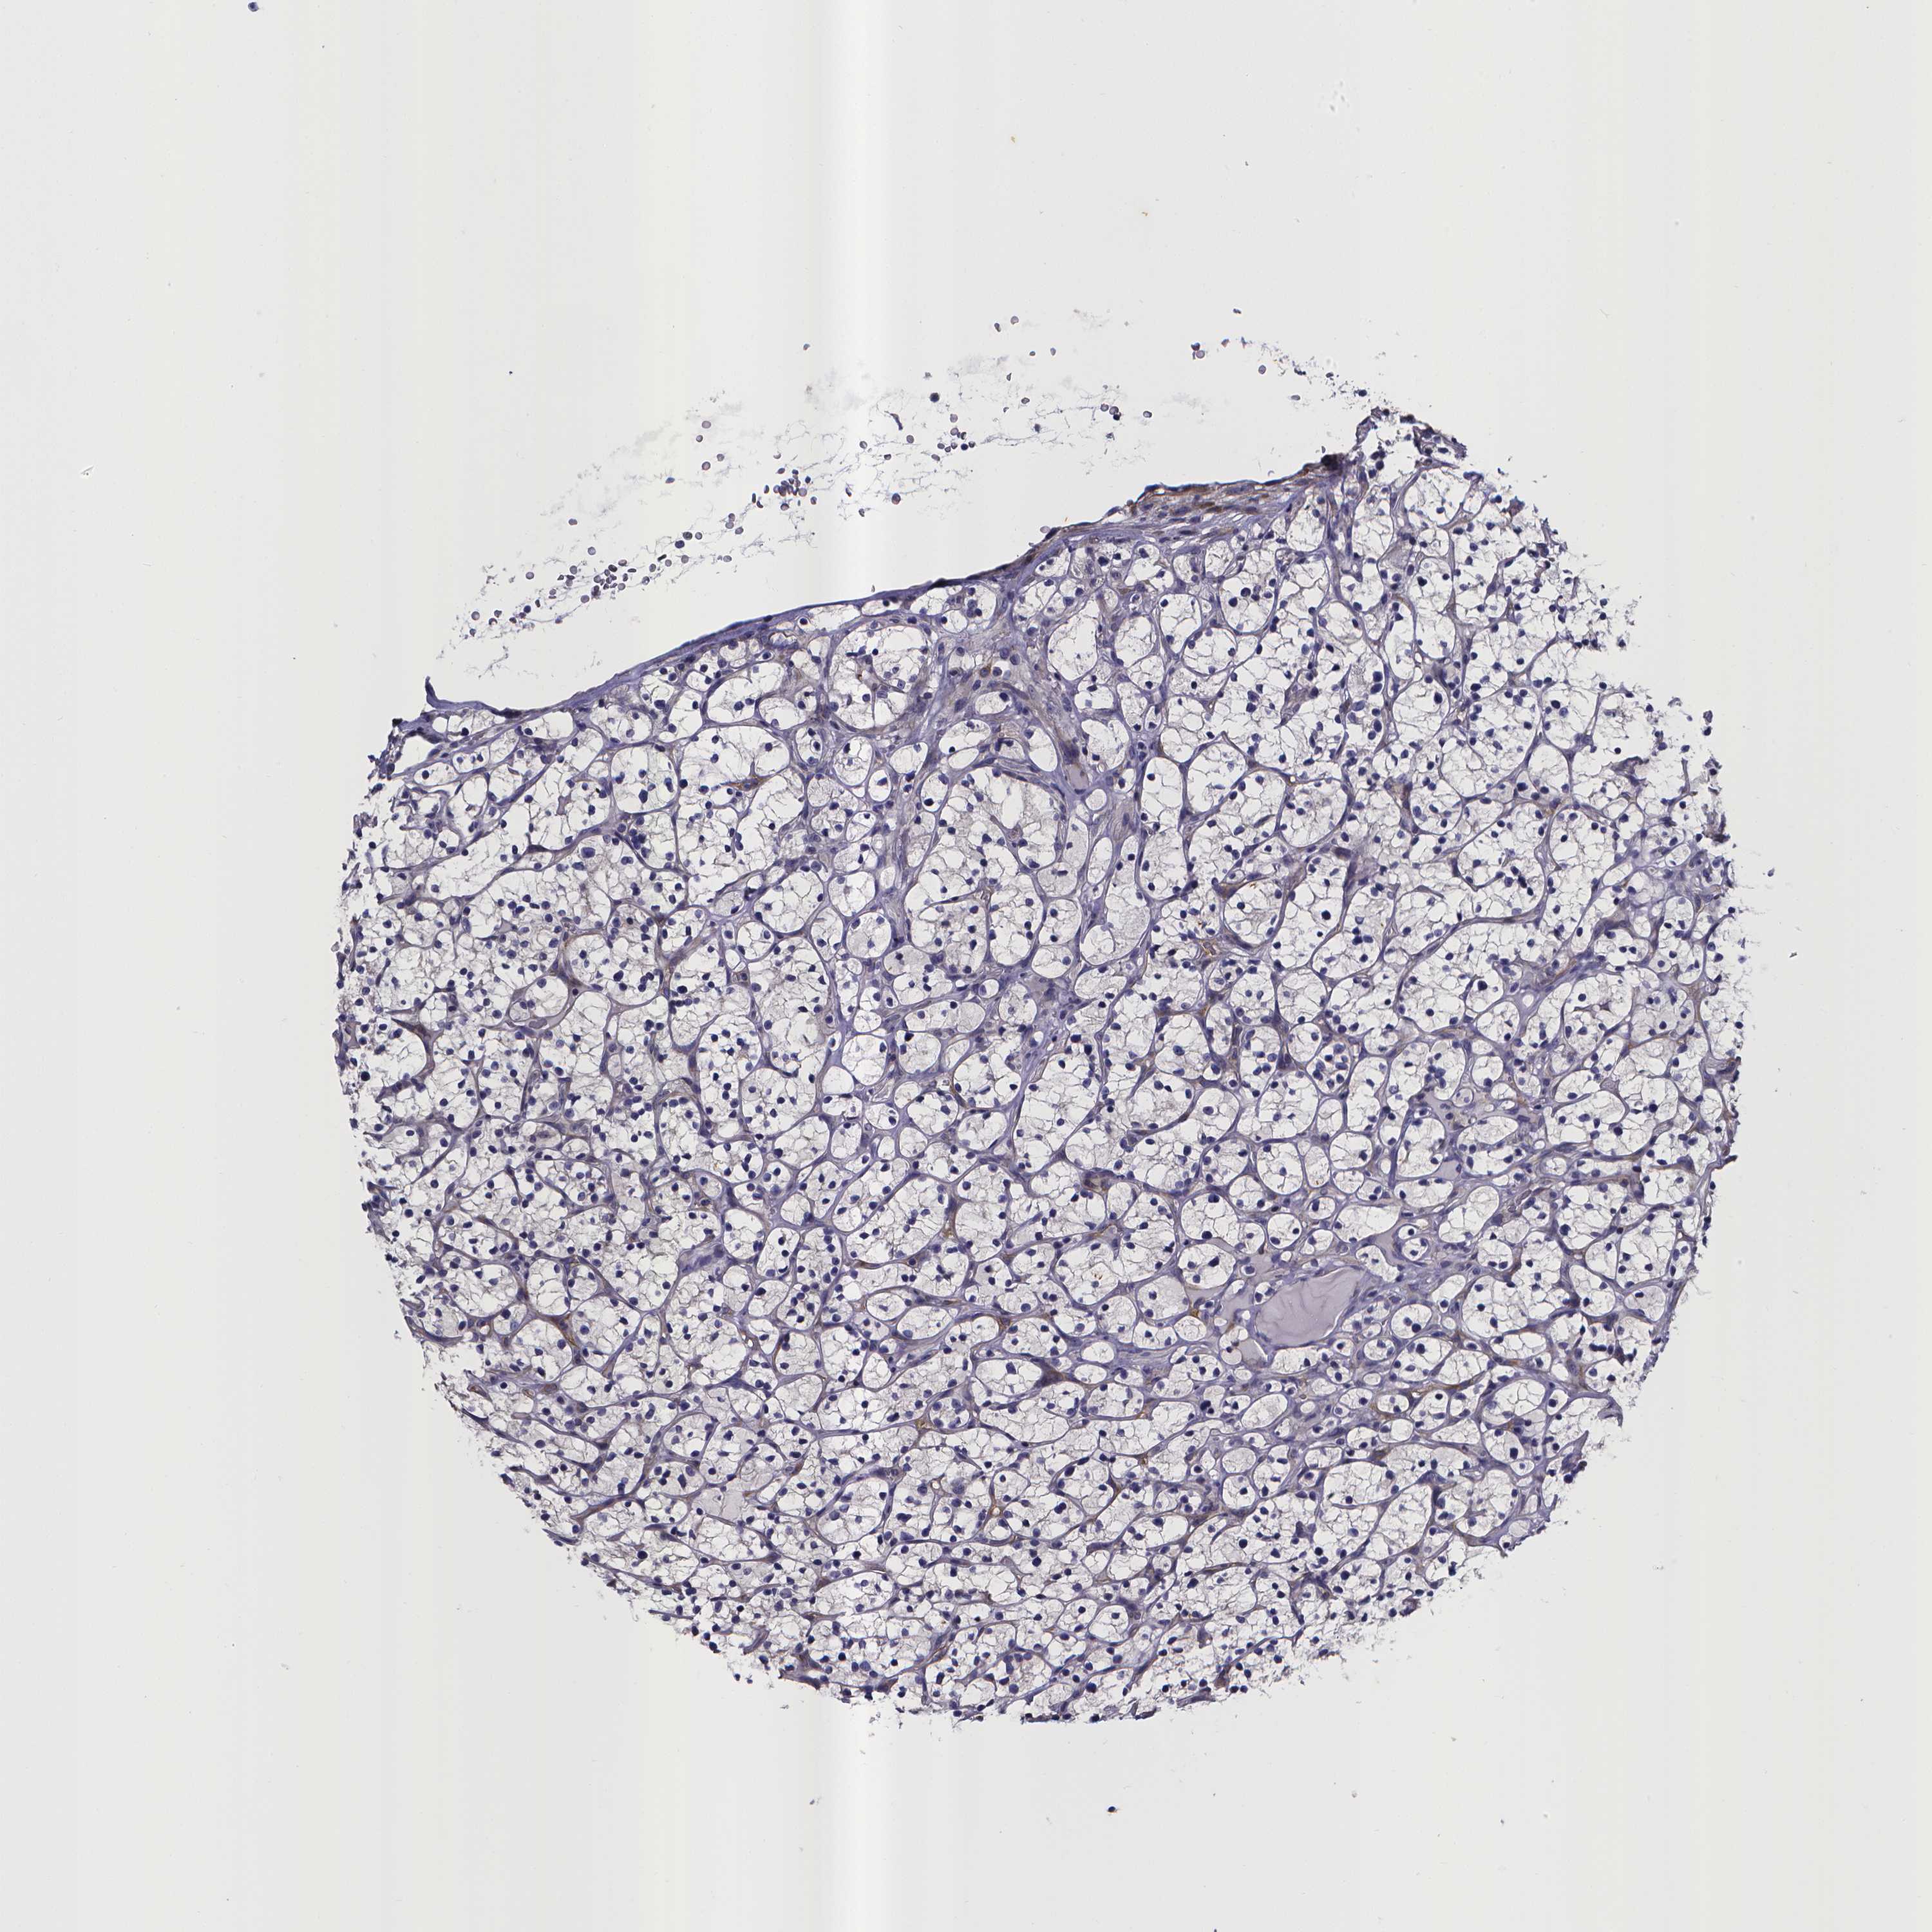

CANCER RENAL CANCER Show tissue menu

KICH TCGA KIRC TCGA KIRC VALIDATION KIRP TCGA PROTEIN RCC CPTAC PROTEIN EXPRESSION

Kidney chromophobe